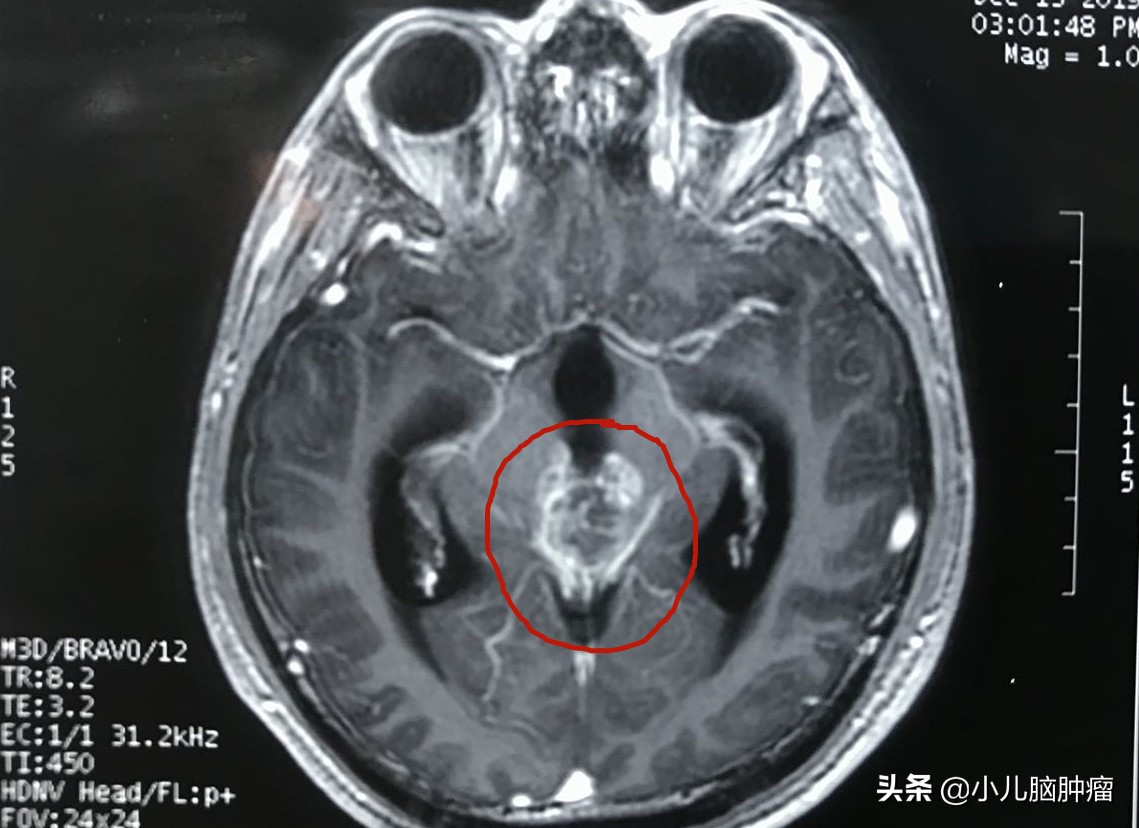

这是一例位于松果体区和三脑室内的肿瘤。

肿瘤压迫并侵犯脑干

肿瘤正好位于脑组织的中心位置

手术结果:肿瘤影像学全切除,病人脑积水解除,术后无神经功能障碍。

手术后复查磁共振,肿瘤消失 ,证明肿瘤被切除了